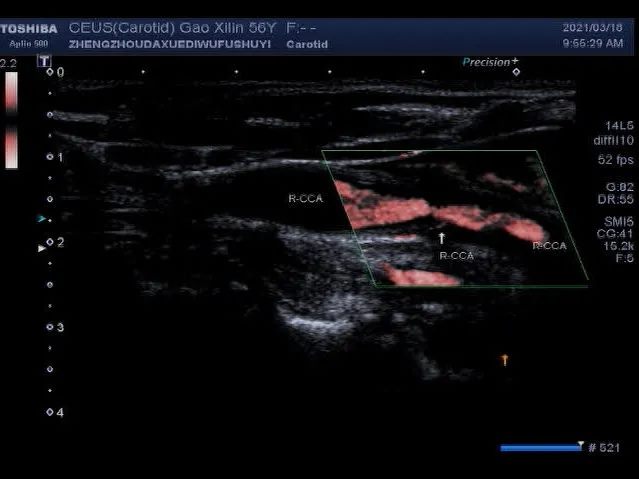

超声微血流技术,称为SMI技术,可以通过识别斑块内低速血流来清晰的显示斑块的新生血管,有助于早期识别易损斑块,为预防脑卒中提供有利的技术支持。

▲ SMI技术显示:白色箭头所指处为斑块新生血管